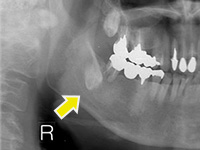

難易度の高い親知らずの抜歯の症例

親知らずが非常に深い位置に、逆さの状態で埋まっていたケースです。右下7番の歯も保存不可能な状態だったため、抜歯しました。